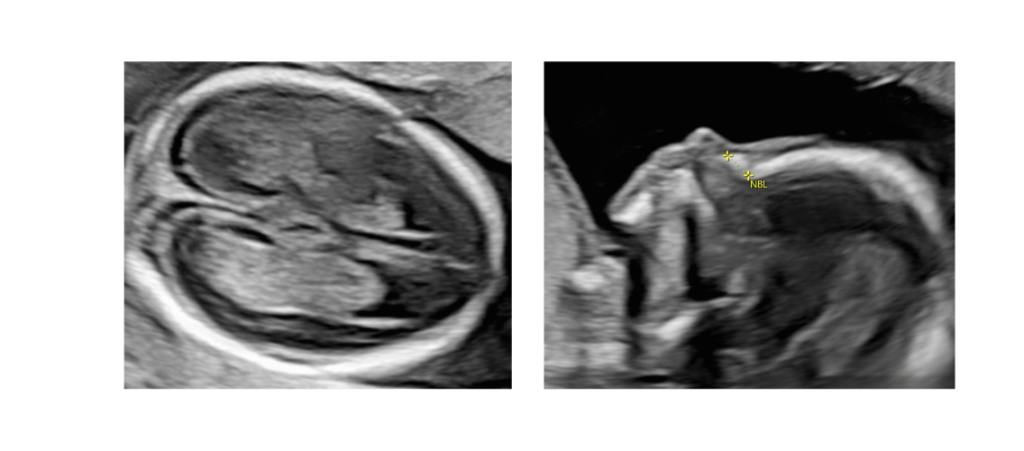

ככל שהעובר גדל, קשה יותר להדגים בבירור את כל איבריו בשל ירידה בכמות מי השפיר והתגרמות העצמות, ולכן בדיקה זו מוגבלת יותר בהשוואה לסקירה השנייה.

בדיקה זו חיונית לאיתור ממצאים שמתגלים לרוב רק בשליש השלישי, כמו הרחבת אגני כליות, ריבוי מי שפיר או הפרעות בגדילה. כמו כן, יש מערכות שממשיכות להתפתח גם בשלב זה – לדוגמה, המוח – ולכן חשוב לבצע סקירה נוספת גם בשליש השלישי.

הסקירה המכוונת מתמקדת במערכת או איבר מסוים – למשל: לב, מוח או כליות – ומשמשת לאישוש, שלילה או השלמת מידע כחלק ממעקב רפואי קפדני.

גולגולת, מוח, פנים, אף, שפתיים, ארובות עיניים

בית החזה: ריאות, לב וכלי דם גדולים

בטן: דופן הבטן, קיבה, כיס המרה, מעי, כליות, שלפוחית השתן

עמוד השדרה, גפיים עליונות ותחתונות